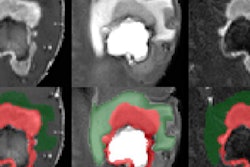

For more complex cases, however, the issue of AI making reliable diagnoses seems less pressing for the moment. Nobody is sure just how far away AI is from making multimodality, multiparametric, or complex MRI diagnoses, but Nikolaou estimates at least 10 years. For example, an algorithm that is trained to detect or even grade prostate cancer from a multiparametric MRI can't differentiate between a significantly higher grade prostate cancer and an inflammation, as it is not trained to do so and does not know about the differential diagnosis of tumor versus inflammation.